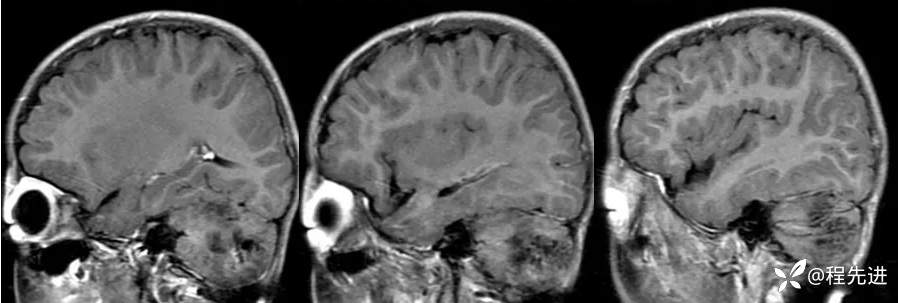

【患者信息】:男,6岁

【主诉】:查体发现左侧小脑半球占位3个月

【现病史及既往史】:患者3个月前因鼻塞至外院就诊,行头颅CT检查偶然发现颅内占位

【检查】